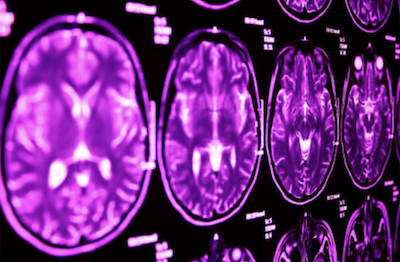

According to Associate Professor Wen, who is Leader of the Neuroimaging Group at CHeBA, brain age is calculated from MRI scans and is considered a powerful index for estimating the underlying biological health of brain tissues.

“We applied advanced technology known as the 3D-CNN deep learning model to measure the grey matter and white matter brain ages separately,” said Dr Du.

The researchers looked at brain scans from nearly 40,000 people with varying levels of blood pressure, ranging from normal to high. They found that as blood pressure increased, both grey and white matter showed signs of ageing, with white matter appearing to age faster.